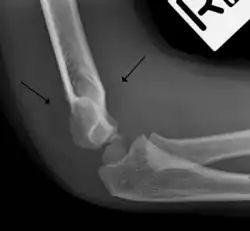

A normal anterior fat pad in a non-fractured arm.